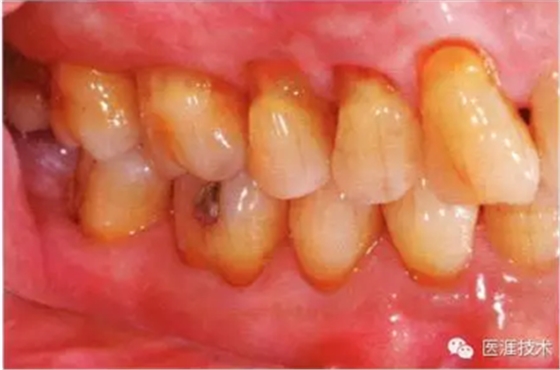

55歲牙周炎男性的臨床照片

55歲男性抽煙患者(1天20支、抽煙35年)。菌斑控制得不好。通過(guò)牙周探診,全頜有4~9mm的牙周袋,有1~3度的根分叉部病變。通過(guò)X光片觀察,上頜前牙中度牙槽骨吸收,其他地方有中度牙槽骨吸收。受吸煙影響,牙齦纖維性肥厚,呈紅黑色。牙齦幾乎沒(méi)有浮腫和發(fā)紅,所以這個(gè)病例是從外觀上無(wú)法預(yù)測(cè)病癥嚴(yán)重程度的病例。